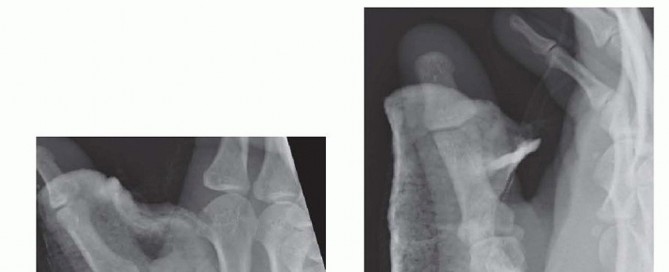

Fixation Strategies for Rolando and Comminuted Patterns

Rolando fractures present a significantly higher degree of complexity. The classical Y or T pattern often precludes simple lag screw fixation. In these instances, mini-fragment plating is the gold standard. T-plates or specialized condylar plates are contoured to fit the complex geometry of the metacarpal base. The articular fragments are first reduced and provisionally pinned, essentially converting the complex intra-articular fracture into a simpler two-part extra-articular fracture. The plate is then applied to buttress the articular fragments and bridge the metaphyseal comminution to the diaphysis.

Image